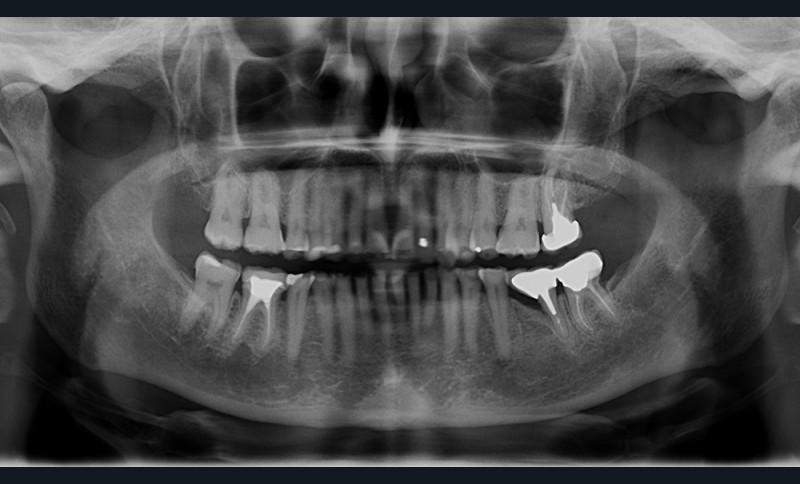

Enfin, une analyse attentive des courbes d’occlusion est menée, notamment dans les cas d’édentements non compensés ou lorsque des restaurations en céramique sont déjà présentes [12] (fig. 1). En effet, la présence de ces dernières peut entraîner une usure différenciée de la dent naturelle antagoniste.

Ainsi, les usures engendrent, dans la majorité des cas, des perturbations au niveau des courbes d’occlusion, lesquelles devront être corrigées lors de la réalisation du wax-up [13].